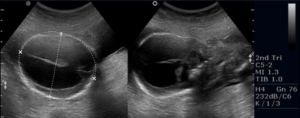

Сканированием измеряют головку будущего ребенка, и основным параметром при этом является ширина желудочков, расположенных сбоку, их размер не должен превышать 10 мм.

УЗИ проводят на 17 неделе и делают повторное исследование на 22 неделе, но средним сроком является 26 неделя беременности. Гидроцефалия на УЗИ плода говорит о наличии сопутствующей инфекции, с которой необходимо начинать бороться немедленно.

Основной метод диагностики – УЗИ. По средствам сканирования измеряют объем и размеры головки малыша, оценивают величину боковых желудочков.

Норма ширины этого показателя составляет 10 мм, превышение этих показателей считается патологическим.